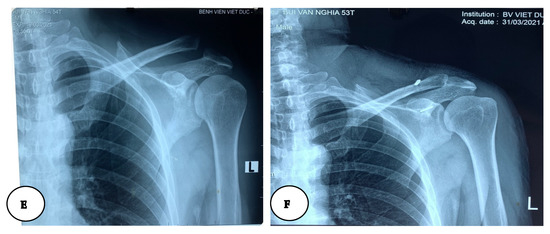

Surgical Techniques and Postoperative Care